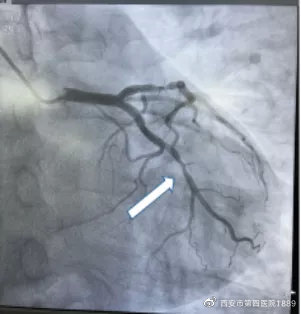

患者辛某,53岁,反复胸闷、胸痛1月。心脏泛血管病院冠心病中心程康教授对患者病情进行详细评估后,分析认为该患者胸痛频发,与活动明显相关,具备比较典型的冠心病症状,遂行冠状动脉造影,发现前降支、回旋支有不同程度狭窄。

前降支临界病变

前降支术前